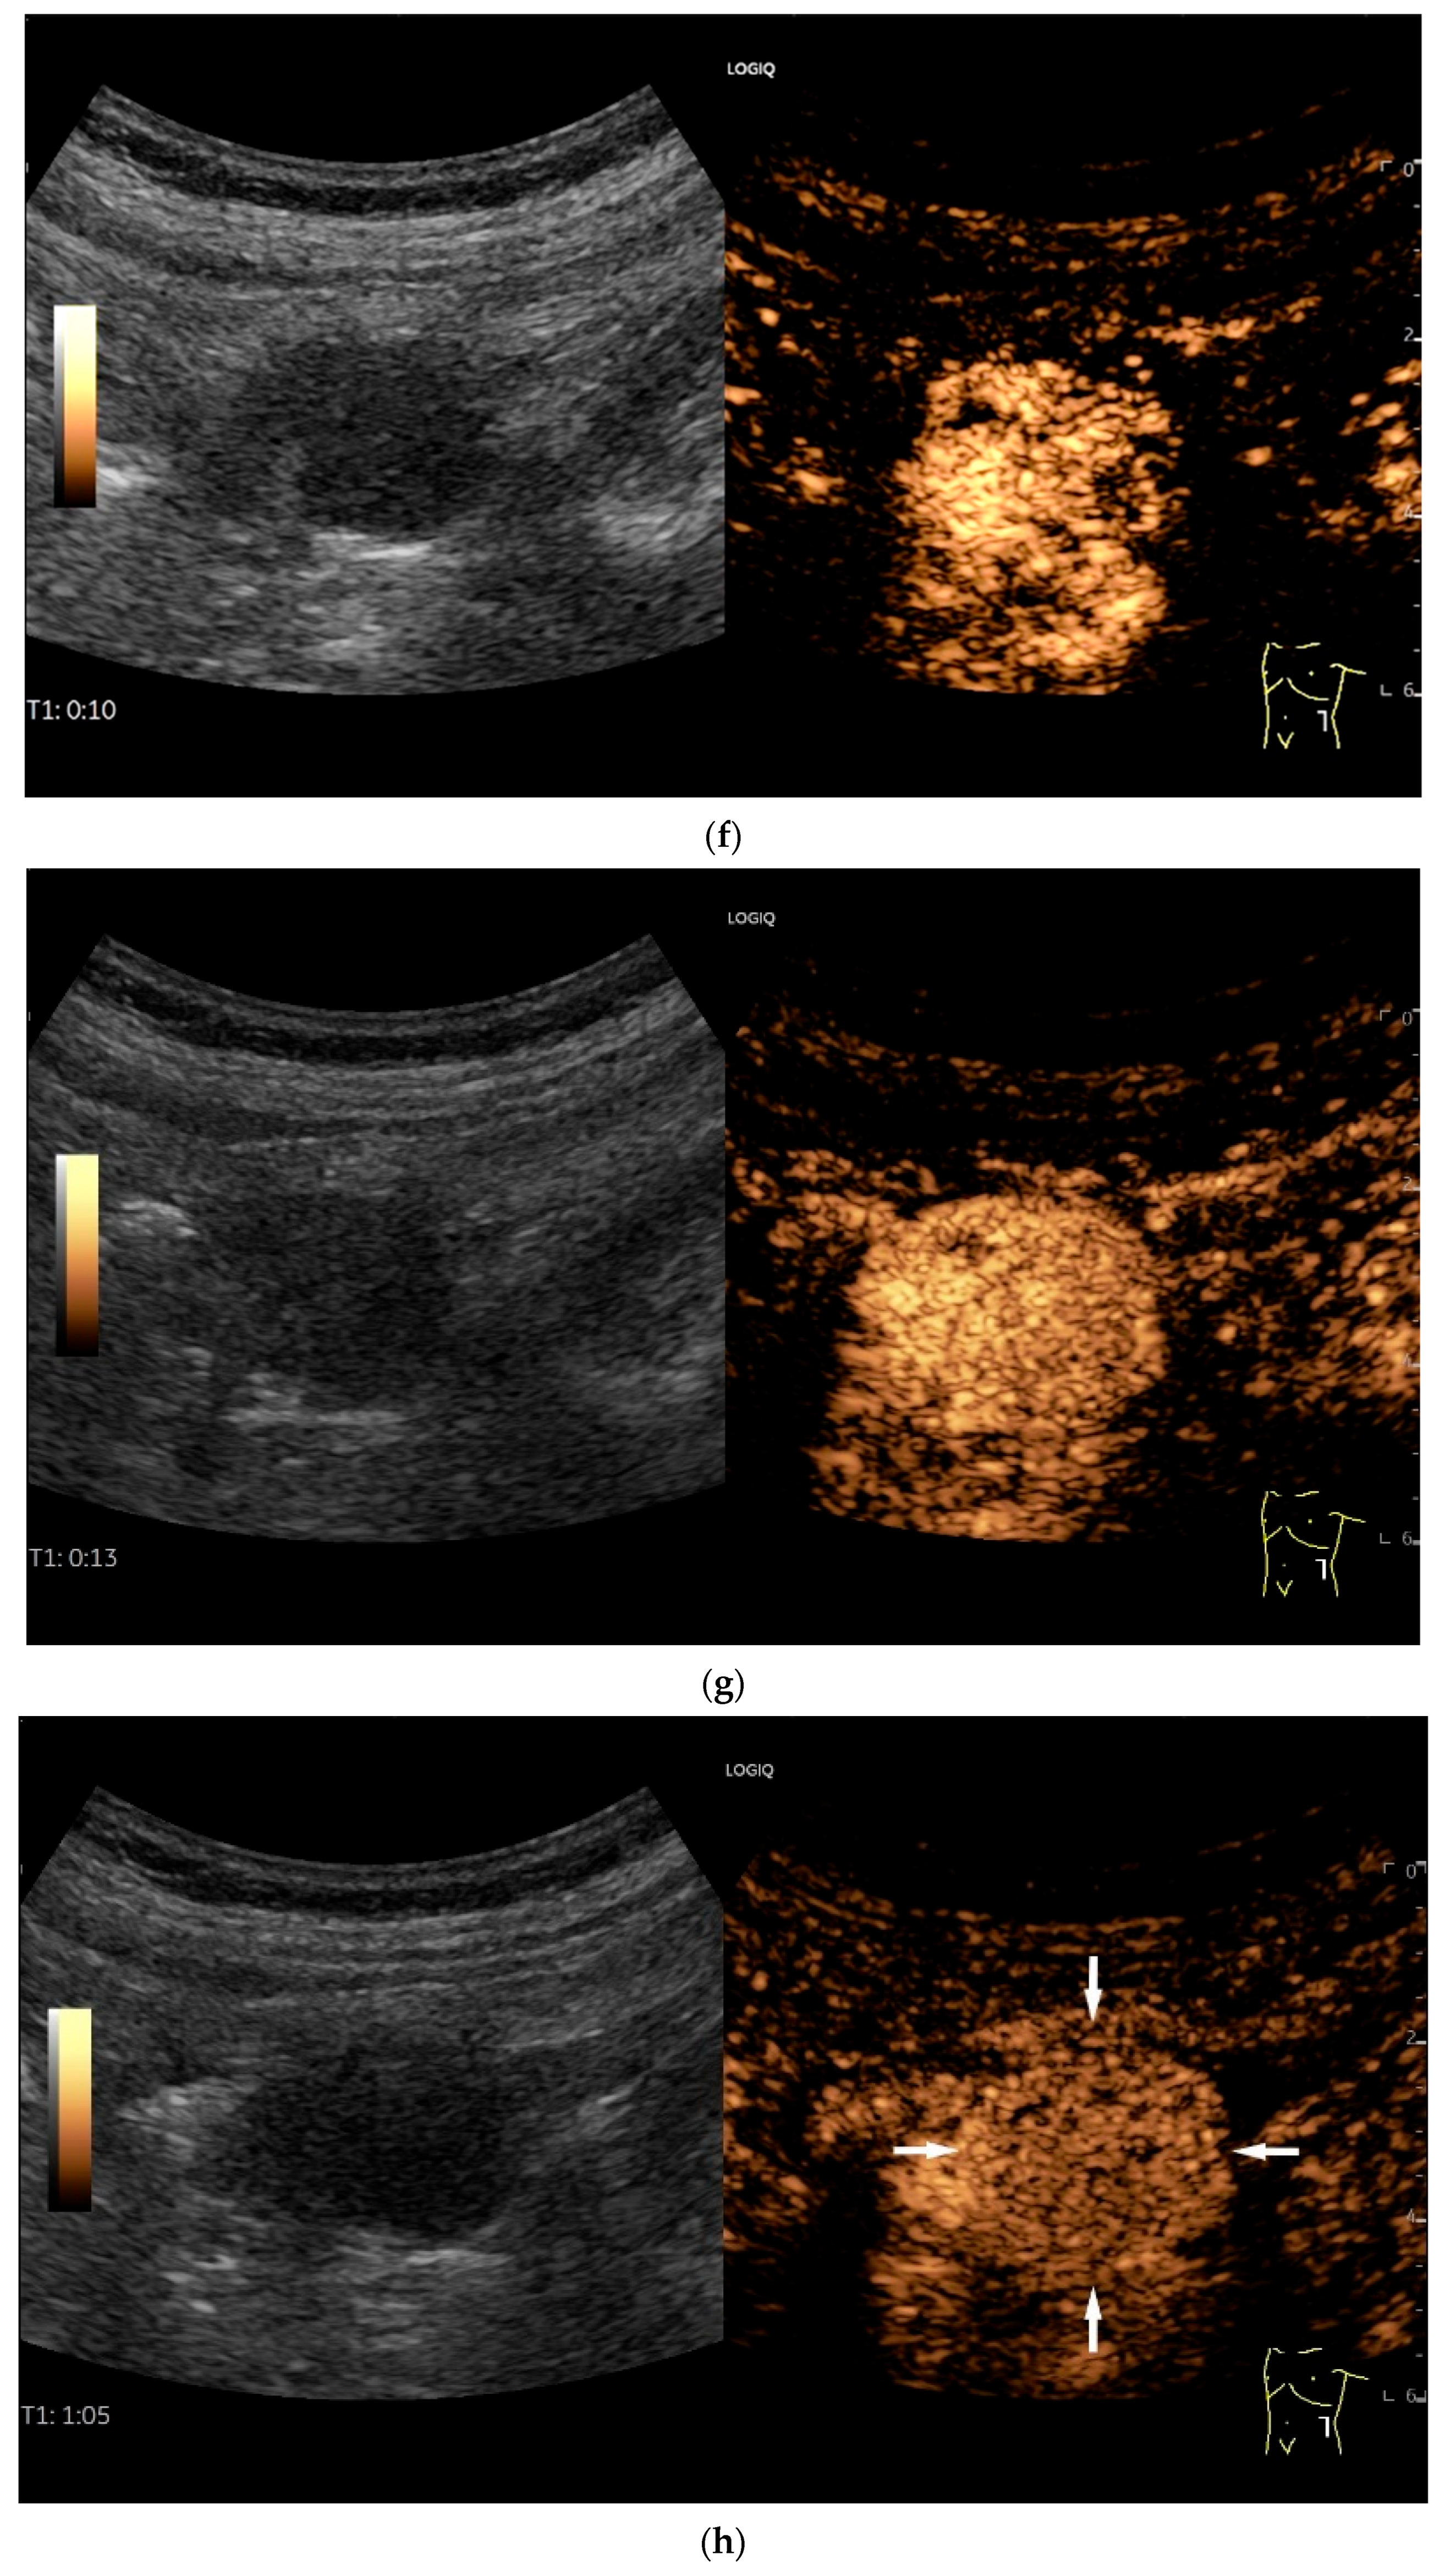

Figure 13.

Inflammatory fibroid tumor (Vanek’s tumor). In cases of unclear occult gastrointestinal bleeding, a smooth-edged oval hypoechoic mass measuring up to 30 mm in size can be seen in the terminal ileum. Examination with the abdominal sector transducer 1–5 MHz (a) and linear transducer 2–9 MHz (b). In power Doppler, a feeding vessel (c) and macro vessels in the mass (d) are visible. In CEUS with 2.4 mL SonoVue using a 9 MHz linear transducer, hyperenhancement is only visible at the edge in the arterial phase. Few vascular signals are visible in the lesion (e). The tumor remains hypoenhanced (f).